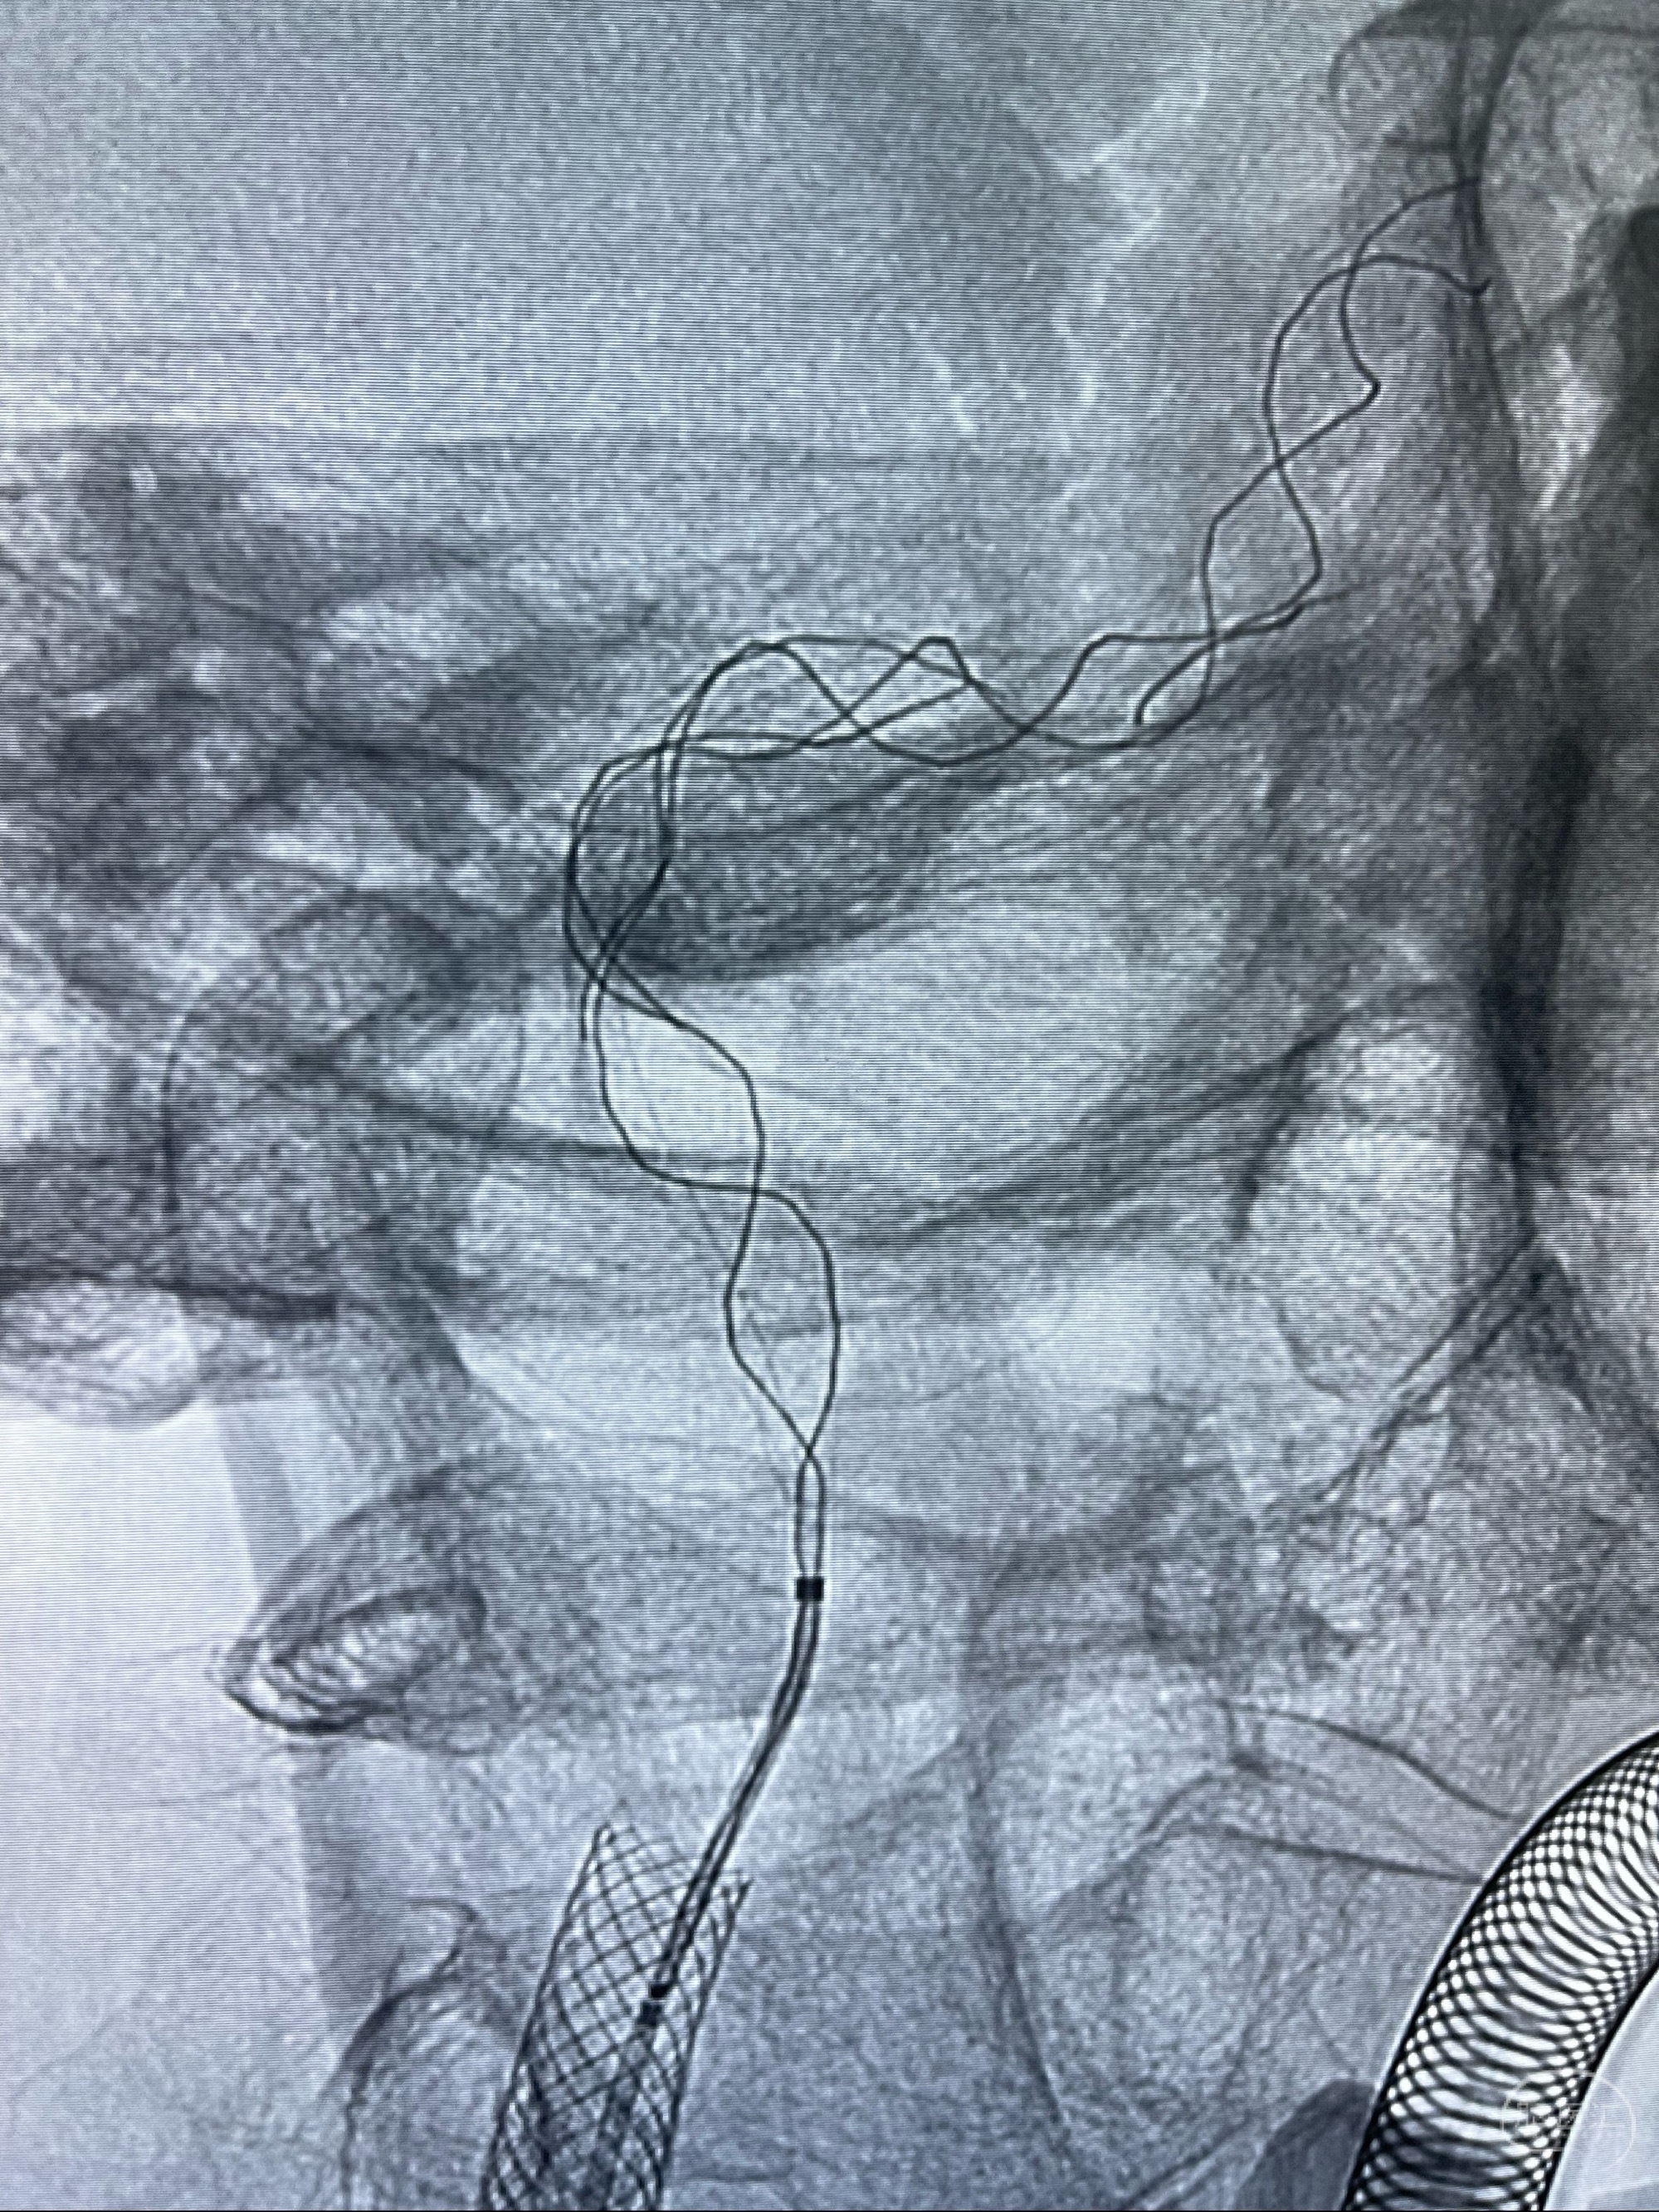

重新行“路径图”,支架导管在微导丝引导下超选择性插入至右侧颈内动脉眼段,4.5-50mmLeo支架释放,远心端位于海绵窦段,近心端位于岩骨段狭窄段以近

即刻造影显示支架贴壁佳

路径图下,5.5-50mmLeo支架导管在微导丝引导下超选择性插入远段Leo支架内

两枚支架部分重叠

多次确认支架位置及打开贴壁情况

支架完全打开,近心端位于原颈动脉支架远心端内